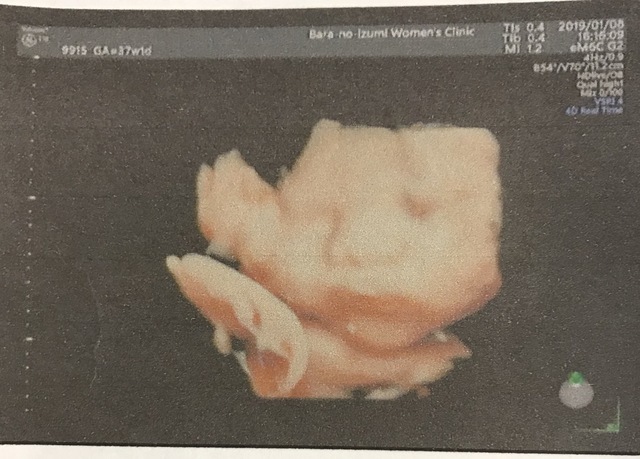

37週6日(37w6d・女の子)|LANIIII さん(23歳)

エコー写真撮影時のエピソード:

生産期に入って初めてしっかり撮れた4Dエコー。パパにそっくりなお顔でニコニコしてる瞬間を見れて愛おしさが爆発しちゃいました